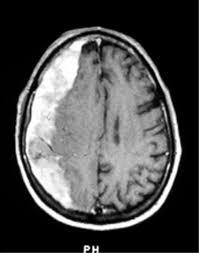

What investigations would you do in someone with suspected subdural haemorrhage?

Imaging - CT/MRI

What might you see on CT/MRI in someone with a subdural haemorrhage?